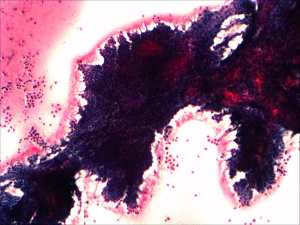

Cytology: resulted in a benign colloid goiter.

Histopathology: benign, dominantly normofollicular adenoma with degenerative changes.